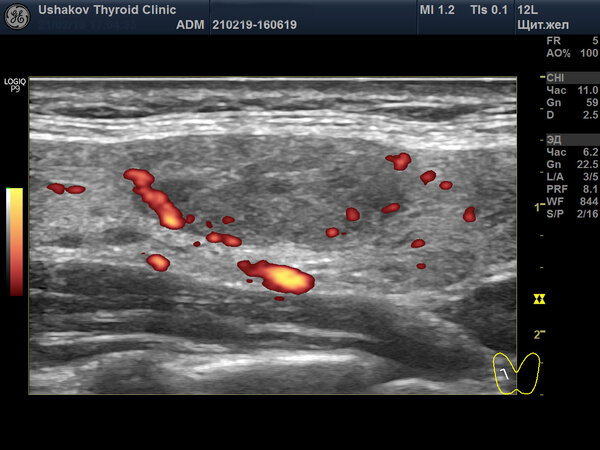

Пример качественного протокола УЗИ щитовидной железы

Для сравнения предлагаем ознакомиться с протоколом, составленным в нашей клинике. Исследование проведено у того же пациента спустя две недели после предыдущего.

Это лишь два снимка из двенадцати, которые были приложены к протоколу. На практике мы распечатываем для пациента от 6 до 25 высококачественных изображений, демонстрирующих все ключевые особенности состояния железы.